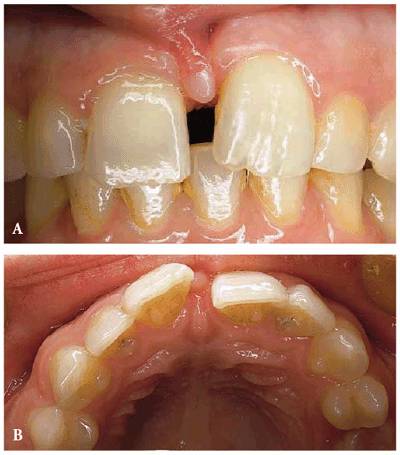

PROBLEM: A 23-year-old female presented with a large maxillary and a

relatively small mandibular diastema (see Figures 23-2A

and B, and 23-2K). The frenum protruded, and the

left central incisor was rotated and in labioversion. Because the patient's

profession was in fashion modeling, her chief complaint was that the presence

of a space between her teeth was a liability to her.

Figure 23-2A and B: This 23-year-old model was dissatisfied not only with the space between her teeth but also with the presence and form of the labial frenum.

TREATMENT: A frenectomy was performed (see Figures 23-2C to

E). After

healing, maxillary and mandibular Hawley retainers were designed for the

patient (see Figure 23-2F). Note how a plastic coating that

conceals the labial wires permitted the patient to wear the appliance while

working. Therefore, she gained the advantage of wearing it more often. Figure 23-2F shows a maxillary appliance in

position and the amount of space needed to close the diastema. Figure 23-2G illustrates the result of wearing

the appliance for 18 hours per day for approximately 4 months. At this point,

the central incisors were mechanically bonded with composite resin to mask the

remaining interdental tissue space (see Figure 23-2H Figures 23-2I

and J show

how facial, mesial, and lingual surfaces were bonded to close the remaining

interdental spaces.

Figure 23-2C to E: The labial frenum was surgically removed so that after her teeth were repositioned there would be no muscle interference.

Figure 23-2F: After the tissue healed, removable Hawley appliances were placed. Note the tooth-colored Teflon tubing applied to the wire to mask the metal color.

Figure 23-2G: After approximately 4 months of wearing the appliance 18 hours per day, the teeth were together.

Figure 23-2H: Composite resin bonding was chosen to close the interdental space between the central incisors.

Figure 23-2I and J: Composite resin bonding is the most conservative method to close an interdental space. (I) Before the restoration. (J) After the restoration outlining the surfaces involved with the restoration.